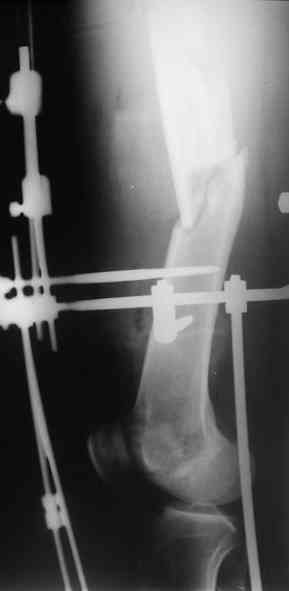

После окончательного заживления раны снять аппарат наложить вытяжение дней на 5-7, посмотреть как ведут себя раны от стержней. Одномоментное снятие аппрата с забиванием гвоздя чревато, сколько, кстати он уже стоит?

Выждав, немного, сделал бы антеградный интрамедуллярный остеосинтез. Насчет того, чтобы винты, фиксирующие мыщелок являлись одновременно блокирующими не согласен - далековато гвоздь забивать придется. Хотя не уверен на 100%

Это интуитивные опасения, или есть конкретный клинический материал, который показал высокий уровень осложнений при одномоментной смене наружного фиксатора на стержень?

Если гноя у спиц-стержней нет даже при сроке в аппарате 6-12 мес., смена по крайней мере на бесканальный титановый штифт относительно

безопасна, глубокая инфекция по нашим данным (~150 таких операций) около 4%.

I> Насчет того, чтобы винты, фиксирующие мыщелок являлись одновременно

I> блокирующими не согласен - далековато гвоздь забивать придется.

А в чем проблемы? Пример в приложении.